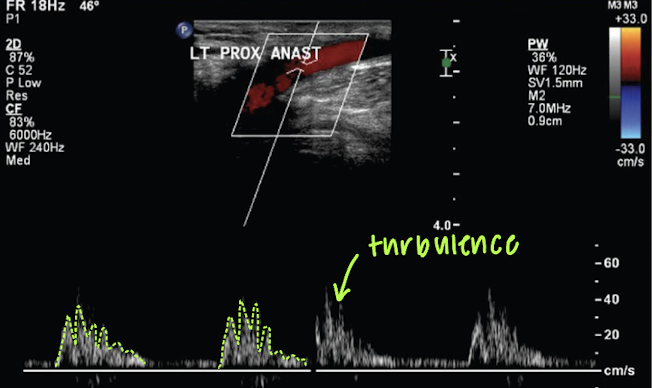

proximal and distal anastomosis may exhibit ____

turbulence (velocity changes)